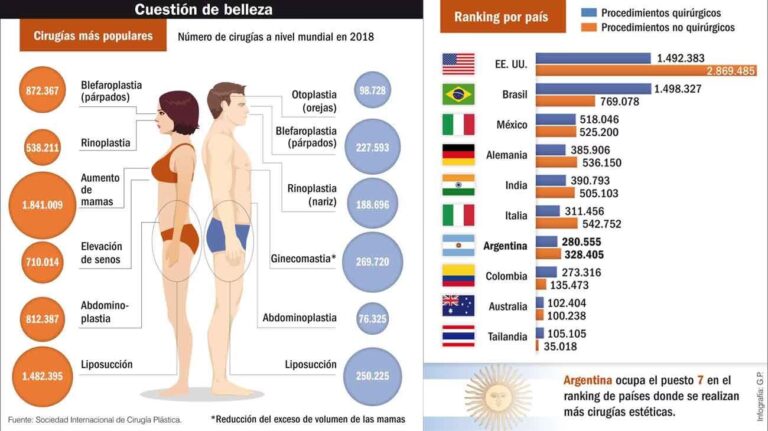

La cirugía estética se enfoca en mejorar la apariencia física para aumentar la autoestima y el bienestar del paciente. Los profesionales uruguayos son conocidos por buscar resultados naturales y armónicos, respetando siempre las proporciones y la individualidad de cada persona. Algunos de los procedimientos más solicitados son la rinoplastia (cirugía de nariz), el aumento o reducción mamaria, la liposucción para modelar el contorno corporal, la abdominoplastia y el rejuvenecimiento facial (lifting, blefaroplastia).